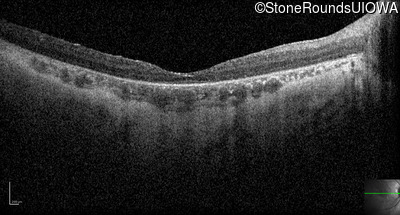

Optical Coherence Tomography - Left - 10/350 sc

Exemplar / OCT Stack

OCT Stack